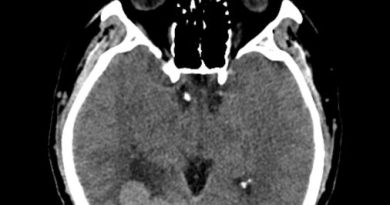

36 yaş, K

Renal transplantasyon, DM+, ateş ve nöbet

Tanınız nedir?